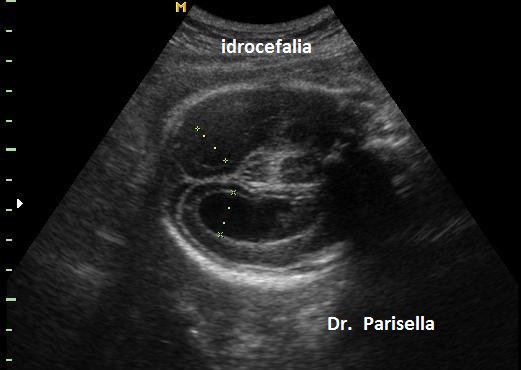

Ecograficamente si caratterizza per la presenza di  ipoplasia del corpo calloso, anomalie di struttura dei pollici (pollici addotti), idrocefalia lieve o moderata.